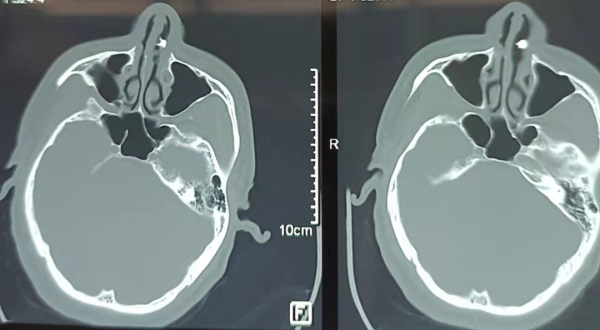

根據臨床經驗,韓永成醫生考慮可能是鼻腔異位牙。拍鼻部CT檢查,發現這個乳白色圓柱狀骨質腫塊,突出至左側鼻腔!大概有3cm長!

根據口腔科醫生會診,齊先生病側上列牙數目不全,故診斷為:左側鼻腔異位牙。臨床影像學結果典型,且具有特異性!應患者及家屬要求,在全麻下鼻內鏡下,拔除牙齒。